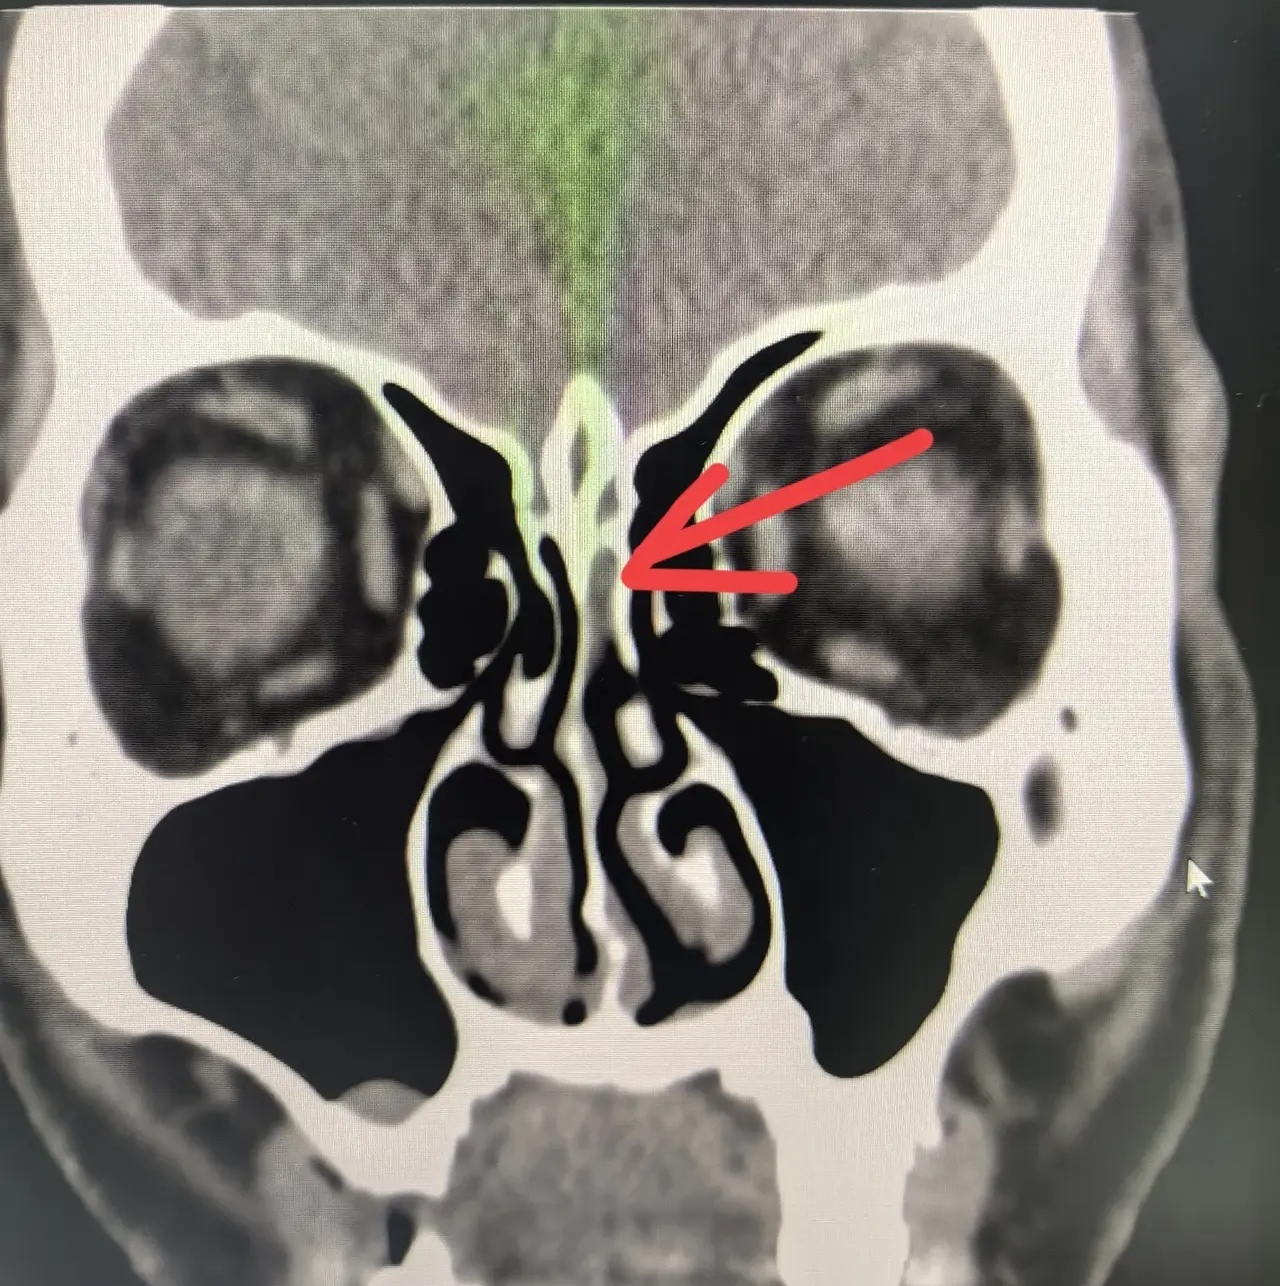

鼻腔突發(fā)間歇性流出清水樣鼻涕2個(gè)月,經(jīng)檢查考慮為自發(fā)性腦脊液鼻漏。該患者是一位船員,經(jīng)常需要重體力活動(dòng),一次用力后出現(xiàn)間歇性左側(cè)鼻腔流清水樣鼻涕,以為流清鼻涕是感冒。近期完成鼻內(nèi)鏡下修補(bǔ)手術(shù),采用的修補(bǔ)材料是轉(zhuǎn)移帶蒂鼻中隔瓣。手術(shù)治療首選鼻內(nèi)鏡下手術(shù),微創(chuàng),但手術(shù)難度較大,容易手術(shù)失敗或出現(xiàn)顱內(nèi)感染等并發(fā)癥。我們?cè)谶@方面有很多的成功經(jīng)驗(yàn),分享給大家。術(shù)中發(fā)現(xiàn)篩竇頂部腦脊液流出